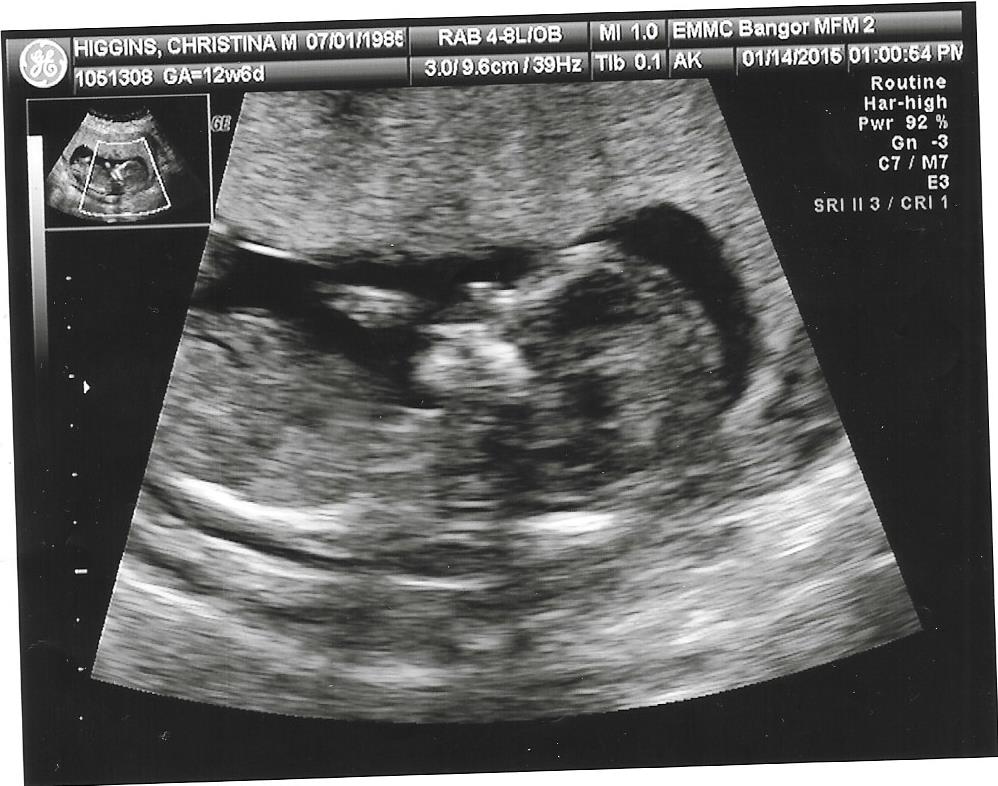

Thank you. Here are the only other 2 shots but they are profile. I heard of nub theory but do not know what to look for.Attachment 23149Attachment 23150

You are looking for a shot like your first one, but sadly was cut off before the nub.

No nub

:( I had a feeling she didn't get it. I assumed it was that white line near the rump.

Yeah the white line you are talking about is just noise from movement. Wish it was the nub so we could give you a better guess. Im looking at your cropped in picture and I would lean boy.